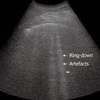

Comet tale artifact: -Caused by closely spaced, highly reflective surfaces -Appears as bright, tapereing lines along the ultrasound beam -short tapering artifact that diminishes in size and intensity with depth -Common in gallbladder adenomyomatosis, likely due to cholesterol crystals in Rokitansky-Aschoff, sinus

Comet tail artifact

Ring down artifact: -Caused by resonant vibrations in air bubbles -Seen in abscesses, emphysematous infections, or any air containing process -Appears as long, continuous, parallel bands, extending deep into the image -Forms when fluid is trapped between a tetrahedron of air bubbles, producing a continuous sound wave

Ring down artifact